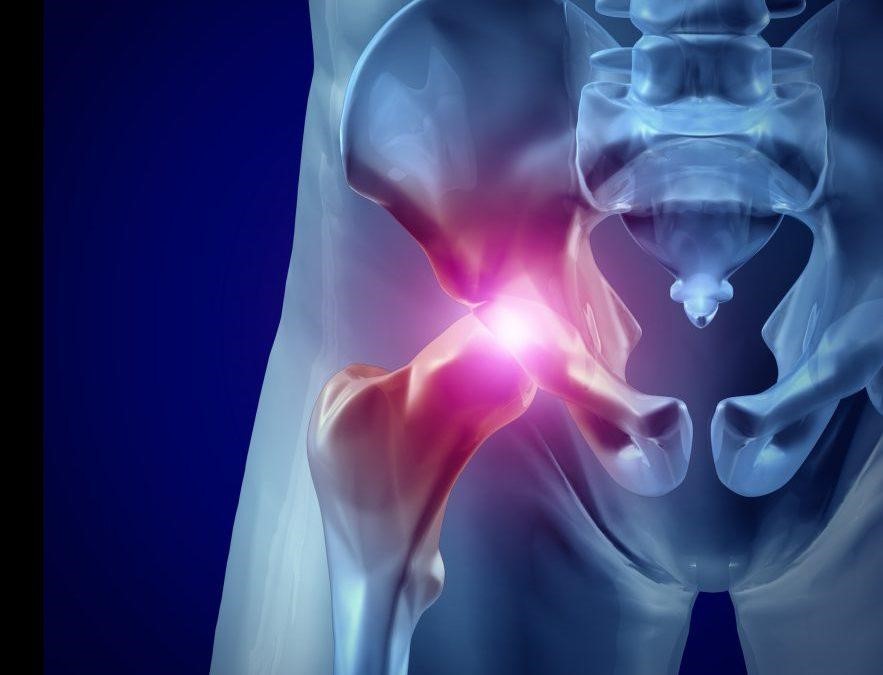

به زبان ساده، آرتروز لگن به حالتی گفته می‌شود که در آن غضروف مفصل لگن، که نقش محافظ و ضربه‌گیر بین استخوان‌ها را دارد، به مرور زمان دچار ساییدگی و فرسایش می‌شود. در نتیجه، استخوان‌ها روی هم سایش پیدا می‌کنند و این موضوع باعث درد، خشکی و محدودیت حرکت می‌گردد. شاید تصور کنید این مشکل فقط برای سالمندان پیش می‌آید، اما واقعیت این است که آرتروز لگن می‌تواند در هر سنی بروز کند؛ از ورزشکارانی که فشار زیادی به مفاصل وارد می‌کنند تا افرادی که به دلیل اضافه‌وزن یا سابقه آسیب‌دیدگی لگن در معرض خطر هستند.

1. درد مفصل لگن یا کشاله ران: این شایع‌ترین علامت است. درد اغلب در هنگام فعالیت (راه رفتن، خم شدن) تشدید می‌شود و در مراحل پیشرفته‌تر حتی هنگام استراحت نیز وجود دارد. جالب است بدانید که گاهی اوقات درد واقعی در ناحیه لگن نیست و به صورت درد ارجاعی در ناحیه کشاله ران، ران یا حتی زانو احساس می‌شود.